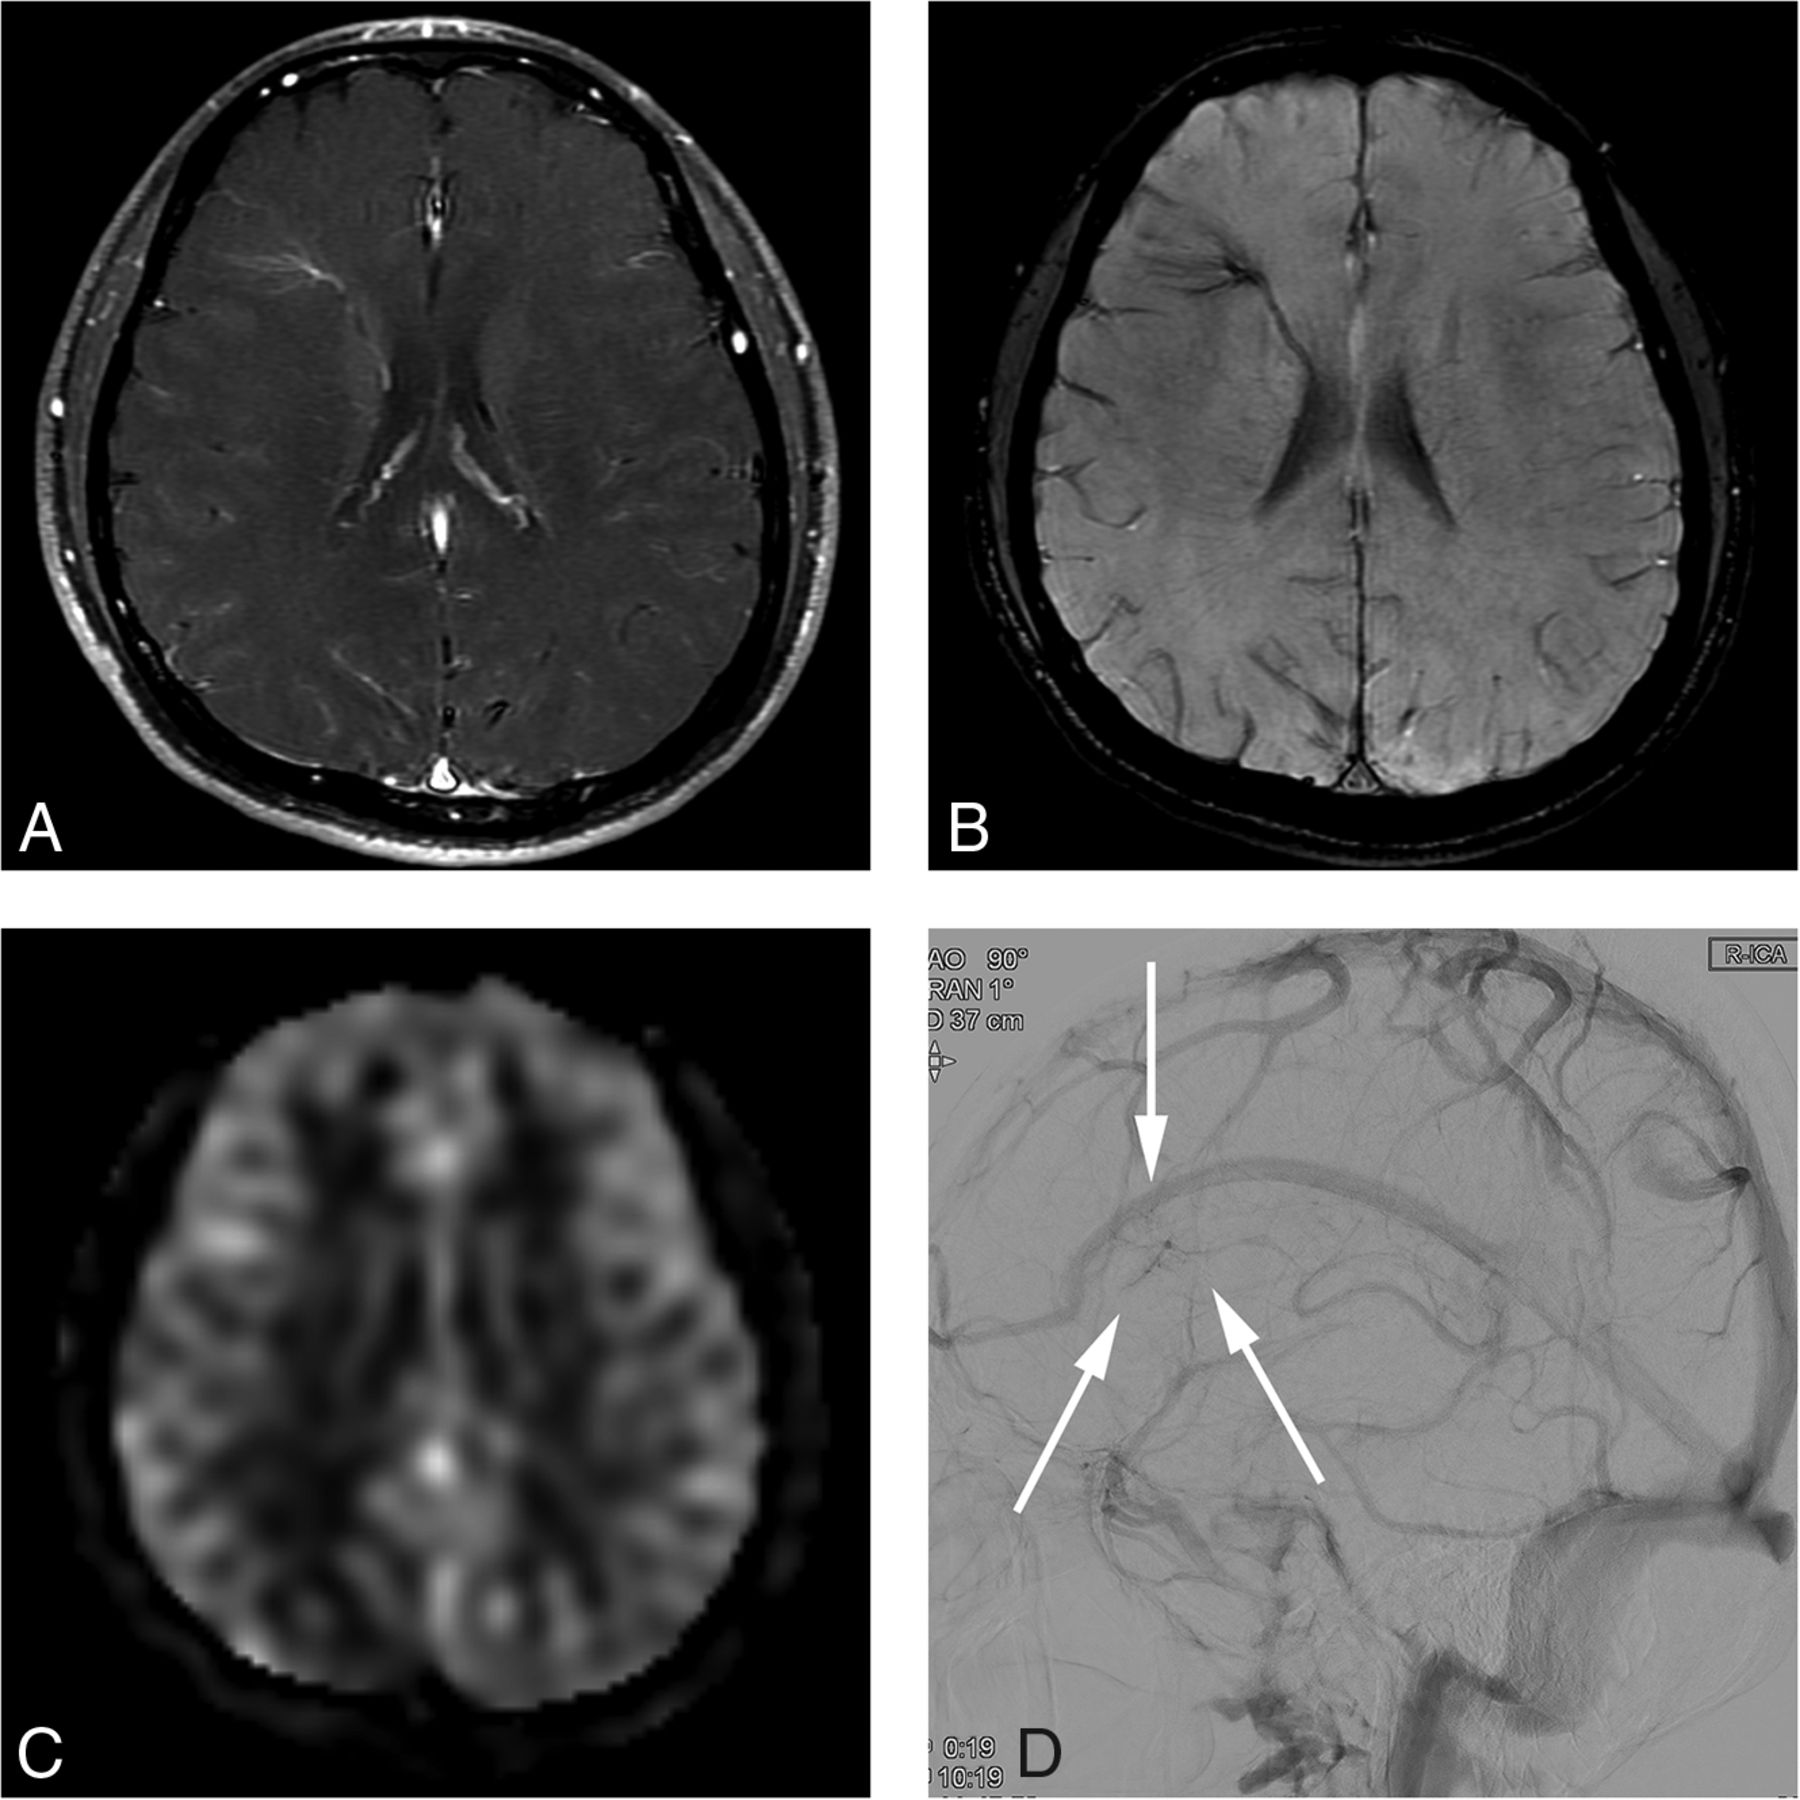

A 31-year-old man presenting with dizziness (case 4). A, Contrast-enhanced T1-weighted axial MR imaging shows a DVA-like lesion in the left frontal lobe. B, On SWI, both hyperintense and hypointense signal is present in the collecting vein, while only hypointense signal is present in the dilated medullary veins. C, The ASL quantitative CBF image demonstrates hyperintense signal intensity in the collecting vein and parenchyma corresponding to the location of the lesion, suggesting a vpAVM. D, On DSA, a caput medusa appearance of medullary veins draining to the superior sagittal sinus via a collecting cortical vein is visualized in the arterial phase.